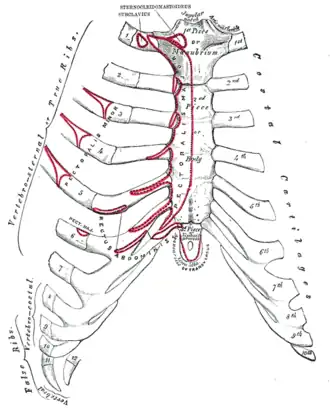

Anterior surface of sternum and costal cartilages.

Anterior surface of sternum and costal cartilages. -